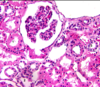

interlobular artery